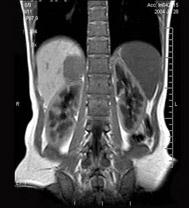

问题 男,31岁,体检时超声发现右肾上腺区病灶,MRI扫描如图所示,下列说法正确的是 ( )

选项 A、考虑为右侧肾上腺髓样脂肪瘤 B、考虑为右侧肾上腺嗜铬细胞瘤 C、该病灶在T1WI为等信号,在T2WI为稍高信号 D、考虑为右侧肾上腺腺瘤 E、右侧肾上腺区可见一类圆形病灶,与周围组织分界清楚

答案 CDE